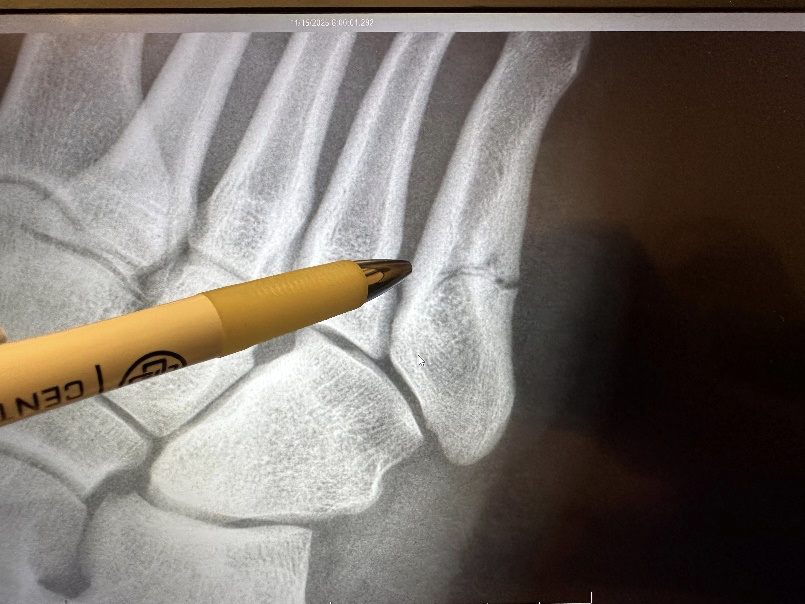

For Wick Kohmescher, a junior football player for Tuttle, the moment came suddenly. During the first round of the playoffs, he felt his foot give way. It didn’t hurt much at first, but something was wrong. An X-ray the next morning confirmed it was a Jones fracture. A notoriously difficult injury to heal because of limited blood flow to that part of the foot.

Surgery went smoothly. X-rays looked good. Remarkably, Wick never needed pain medication either—not even ibuprofen. Less than a week later, he was putting weight on his foot. 18 days after surgery, he was back at practice.